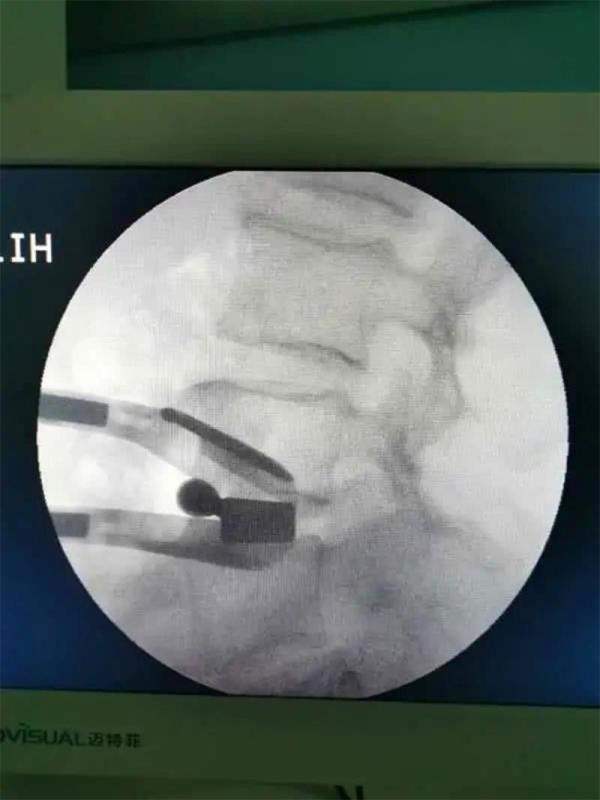

通过不到5cm的小切口,切除了椎间盘并植入大尺寸融合器,手术出血不到10毫升。术后当天,患者就感觉腰腿痛明显缓解,术后第2天已经能下床行走。该项技术的成功实施,标志着昆明市中医医院骨伤科脊柱微创水平再上新台阶。

OLIF于2012年由法国Silvestre等首先报道,是一种新的微创技术,该手术经左下腹腹外斜肌、腹内斜肌、腹横肌的肌间隙进入腹膜外间隙,在左侧腰大肌和腹主动脉之间安放工作通道,通过大血管间隙及腰大肌间入路进行手术,可明显减少手术创伤、缩短手术时间、减少术中出血、缩短住院时间及患者康复时间。

2.操作时避让开了重要血管,也不需要咬除骨头,术中出血不到10毫升,切口也仅有4—5厘米左右;